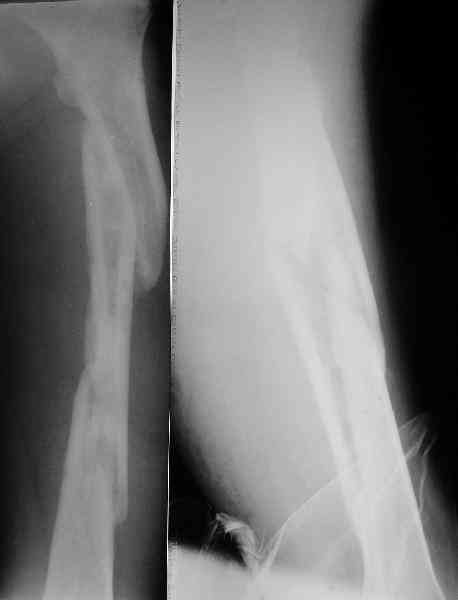

Уважаемые коллеги! Пришел на консультацию вот такой больной (первые 3-и рисунка). Травма автодорожная, апрель 2006г. Лечился консервативно, вытяжение и гипс. Через пять месяцев стал ходить. Укорочение бедра 6 см. 26 февраля 2007г. оступился, упал. Прооперирован в г.Баку - наложен стержневой аппарат. Ходит с костылями, наступая на левую ногу. Мы попросили что нибудь из ранних снимков. Принес рентгенограммы перелома (рис. 4,5). Посмотрели, наснимали сами (рис. 6-10). Похоже, что нет сращения нигде. Хотелось - бы обсудить следующие вопросы:1. дальнейшая тактика - реостеосинтез или подождать (ослабить аппарат, дать нагрузку и т.д.)?2. если реостеосинтез - то чем и как? Юрий Алексеевич Булахтин

Юрий Алексеевич. Привет. А сустав тазобедренный живой? На одном из снимков он возник - но качество рентгенограммы - швах. Если он жживой то я бы сделал

гвоздь с блокированием, через некоторое время после снятия аппрата, вмешиваясь на больших углах малоинвазивно. А если нет.....То стоит подумать

об ТHR с очень длинной ножкой. А Рыков. Хабаровск.